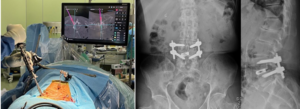

内視鏡下椎体間固定術の様子と術後のエックス線画像

③ 内視鏡下椎体間固定術(ME-LIF、PET-LIF)

脊椎不安定性や側弯変形を認める場合には固定術を検討する場合があります。そのような症例に内視鏡を用いて腰椎後方椎体間固定術を行います。MEDを応用した方法(ME-LIF)と、FESSを応用した方法(PET-LIF)があります。内視鏡を利用することで手術の低侵襲化が可能となり、従来法の手術に比べて早期離床や早期退院が可能になります。また術後の感染や術後血腫などが従来法と比較して低減できるメリットがあると考えています。